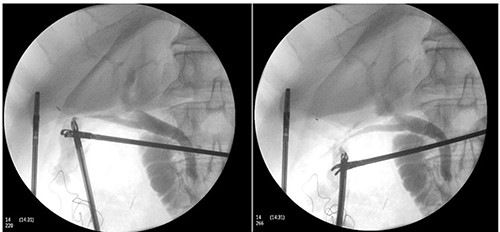

Perioperatively, retrograde dissection of gallbladder was performed due to gallbladder being thick, fibrotic, intrahepatic and access to Calot’s triangle was obscured by dense omental adhesions. Gallbladder was opened at Hartman’s pouch to perform an intraoperative cholangiogram safely; two bile-flowing tube structures were found at base of Hartman’s (Fig. 1). Intraoperative cholangiogram catheter was only able to be performed via one of the two ducts with no evidence of leak (Fig. 2). A Hepatobiliary Surgeon was consulted intraoperatively, the decision was to complete a subtotal cholecystectomy with the stump, containing both lumens, secured with Endoloop ties. 15F Blakes drain was placed at the gallbladder bed.

Intraoperative cholangiogram performed via one of two duct structures; double cystic duct not evident.